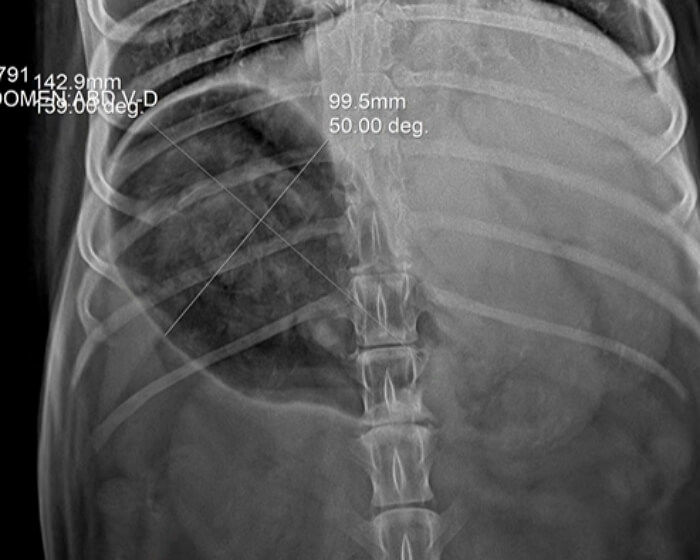

걱정된 집사가 급히 병원을 찾았는데요. 엑스레이 검사 결과 허스키 강아지 모의 배 속에는 아주 선명한 거북이 등껍질 두 개가 자리 잡고 있었습니다.

거북이를 장난감으로 착각해 삼켜버린 허스키 강아지 모는 장염과 복부 팽만으로 고통스러워했어요. 하지만 허스키 강아지 모는 이미 9살로 나이가 꽤 많은 편이라 전신 마취를 하고 수술을 하기에는 위험이 너무 컸죠.

그래서 수의사 선생님은 수술 대신 장 운동을 돕는 소화제와 배설을 돕는 약을 처방하며 자연적으로 나오기를 기다리기로 했습니다.